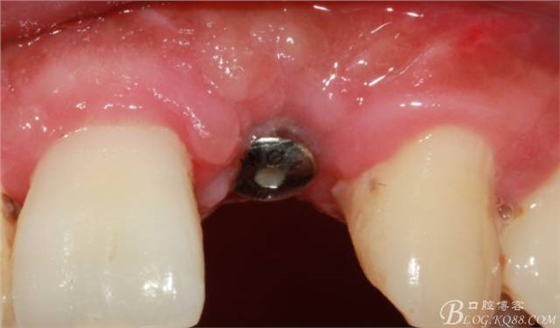

10天拆線一切正常,又過了兩周患者復(fù)診,自述期間無異常??趦?nèi)檢查,真的嚇了一跳,唇側(cè)鼓了個包,擠壓有白色分泌物溢出,絕對不是膿液,液體排除后,術(shù)區(qū)觸診空虛,外觀塌陷。這時候考研大夫的時刻到了,是先觀察一段時間再說?還是馬上進(jìn)行處理?我的回答是:馬上處理!如果你沒有及時處理,而是放患者回家觀察,那么接下來會發(fā)生如下情況:1.回家后患者家屬及親友會有很多你可以想象得到的討論;2.患者及家屬會對你產(chǎn)生不信任,勢必會到其他門診或醫(yī)院檢查,他院大夫會不會發(fā)表對你不利的言論;3甚至?xí)蚁嚓P(guān)法律界人士找你討要說法。

于是我果斷告知患者,手術(shù)失敗了,不能拖延,如不及時處理,炎癥繼續(xù)發(fā)展會很快波及鄰牙牙槽骨。患者接受我的建議。切開翻瓣,骨粉及生物膜消失了,骨吸收嚴(yán)重,幸運的是,因為處理及時,鄰牙骨支持依然存在。